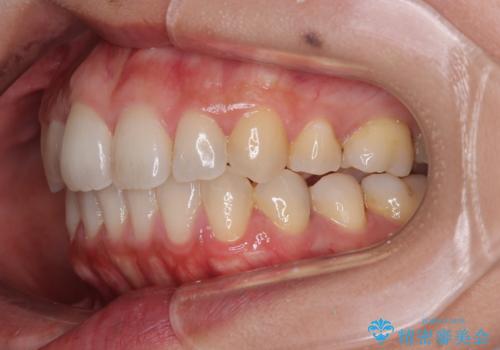

前歯のデコボコを改善 インビザラインの矯正治療

- 前歯のデコボコを治したいとのことで来院された患者様です。

上下顎ともに歯列全体の後方移動とIPR(歯と歯の間を削る)によってデコボコが解消するように設計し、インビザラインにより治療を行うこととしました。